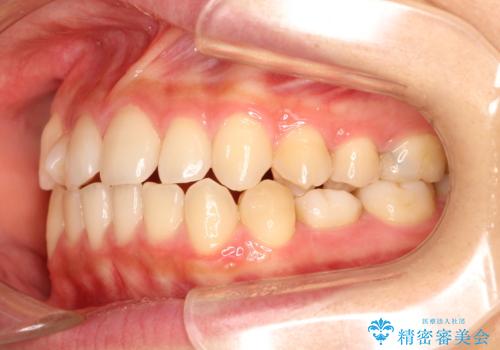

- 前歯の捻れを主訴に来院されました。

インビザラインを希望されておりましたが、20時間もつけることができなかったためワイヤー矯正にて叢生の改善を行っています。

右上の側切歯(前から2番目の歯)が90度程度ねじれている状態でしたが、1月に1回のワイヤー交換できれいに並ぶことができ満足いただけました。

捻れた歯の治療に関しては、ワイヤー矯正の方が仕上がりがきれいに治りやすいです。